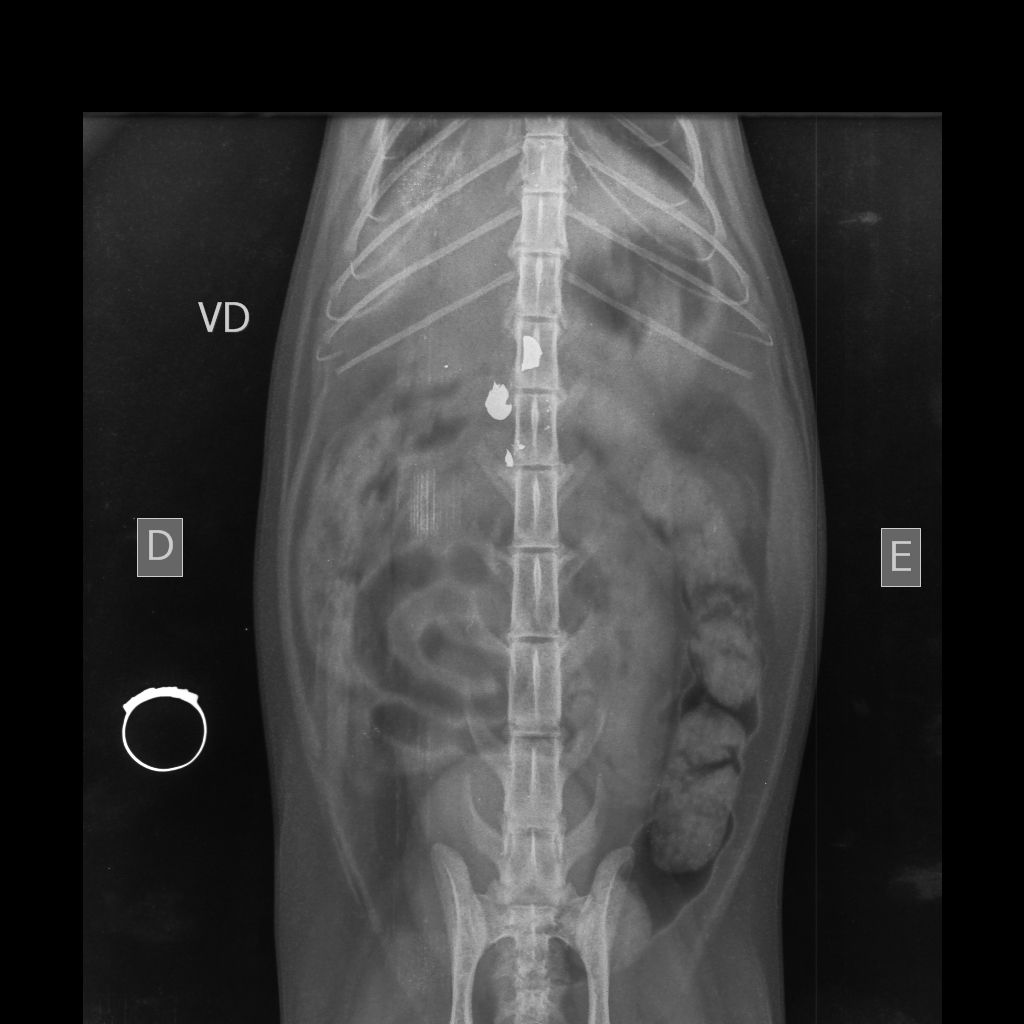

A gata, chamada Morgana, está sob os cuidados da clínica veterinária Vida Pets. De acordo com os responsáveis pelo animal, ela encontra-se estável e passa por exames antes da cirurgia. Os tutores já prestaram depoimento à Polícia Civil e afirmaram que irão acompanhar o caso até o fim. A família também agradeceu a mobilização da comunidade.

O caso veio à tona após a Polícia Militar do Paraná (PMPR) ser acionada via 190. Conforme relato do tutor, ele estava no pátio da residência com a esposa, por volta das 18h00, quando ouviu um estampido. Em seguida, a gata, que estava sobre o muro da casa, caiu ferida. O animal apresentava lesão compatível com projétil, embora inicialmente não fosse possível identificar se o disparo partiu de arma de fogo ou arma de pressão.